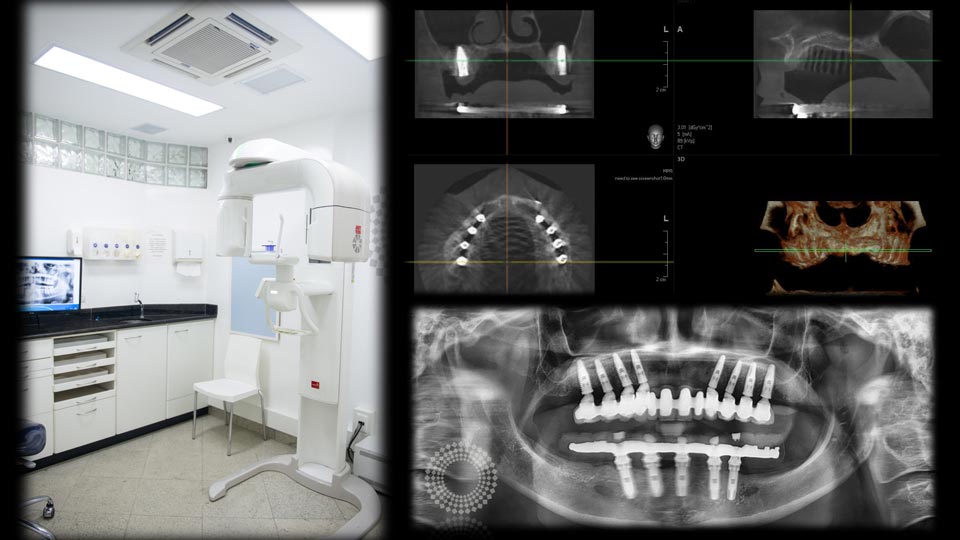

Radiografia Panorâmica e Tomografia 3D

Todos os tratamentos são planejados e acompanhados por imagens radiográficas e tomográficas digitais, sem que o paciente precise procurar outro local para a realização desses exames